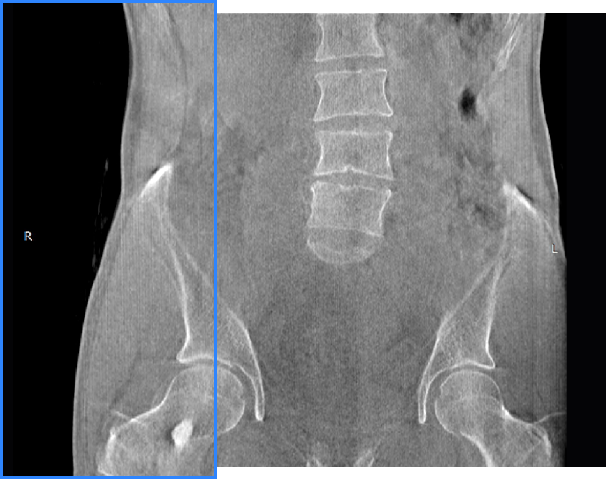

髋关节

FOV 250mm

FOV 350mm

关闭金属伪影校正

开启金属伪影校正